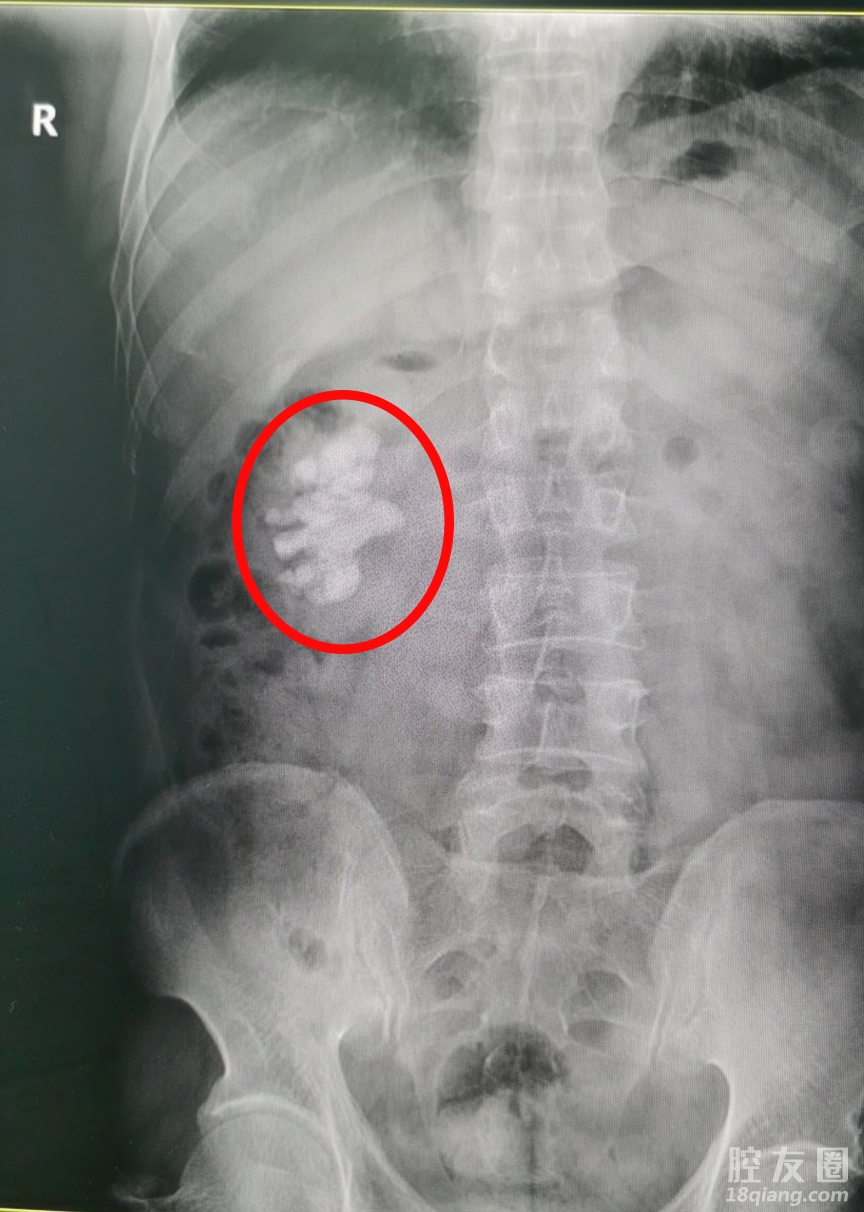

根据病情,我院泌尿外科医生为其行超声、CT等检查,结果显示患者右肾有巨大结石,这在泌尿外科专业称之为鹿角型结石,为肾结石中最复杂、最巨大、最难处理的结石类型!随后赵先生入院进一步手术治疗。

“最开始检查出来,结石才一点点,所有也就没在意,这么多年,经常性的应酬,酒肉不断,也没想到要去控制,没想到竟然变成了这样……。”看着自己CT报告单上类似鹿角的巨大结石,赵先生始终不敢相信。

627日上午,在经过充足的术前准备,赵先生被送入手术室。术中通过B超了解肾结构,明确结石位置、大小,结石与周围肾盏关系明确,确定体表穿刺点,给皮肤做一小切口,穿刺建立微通道,通过输尿管镜可见结石,经过钬激光装置,在可视下将结石彻底击碎并清除,经过谢主任及手术室医护人员的全力配合,穿刺一针到位。2小时后,手术顺利结束,术中取出的碎石碎块高达100颗。